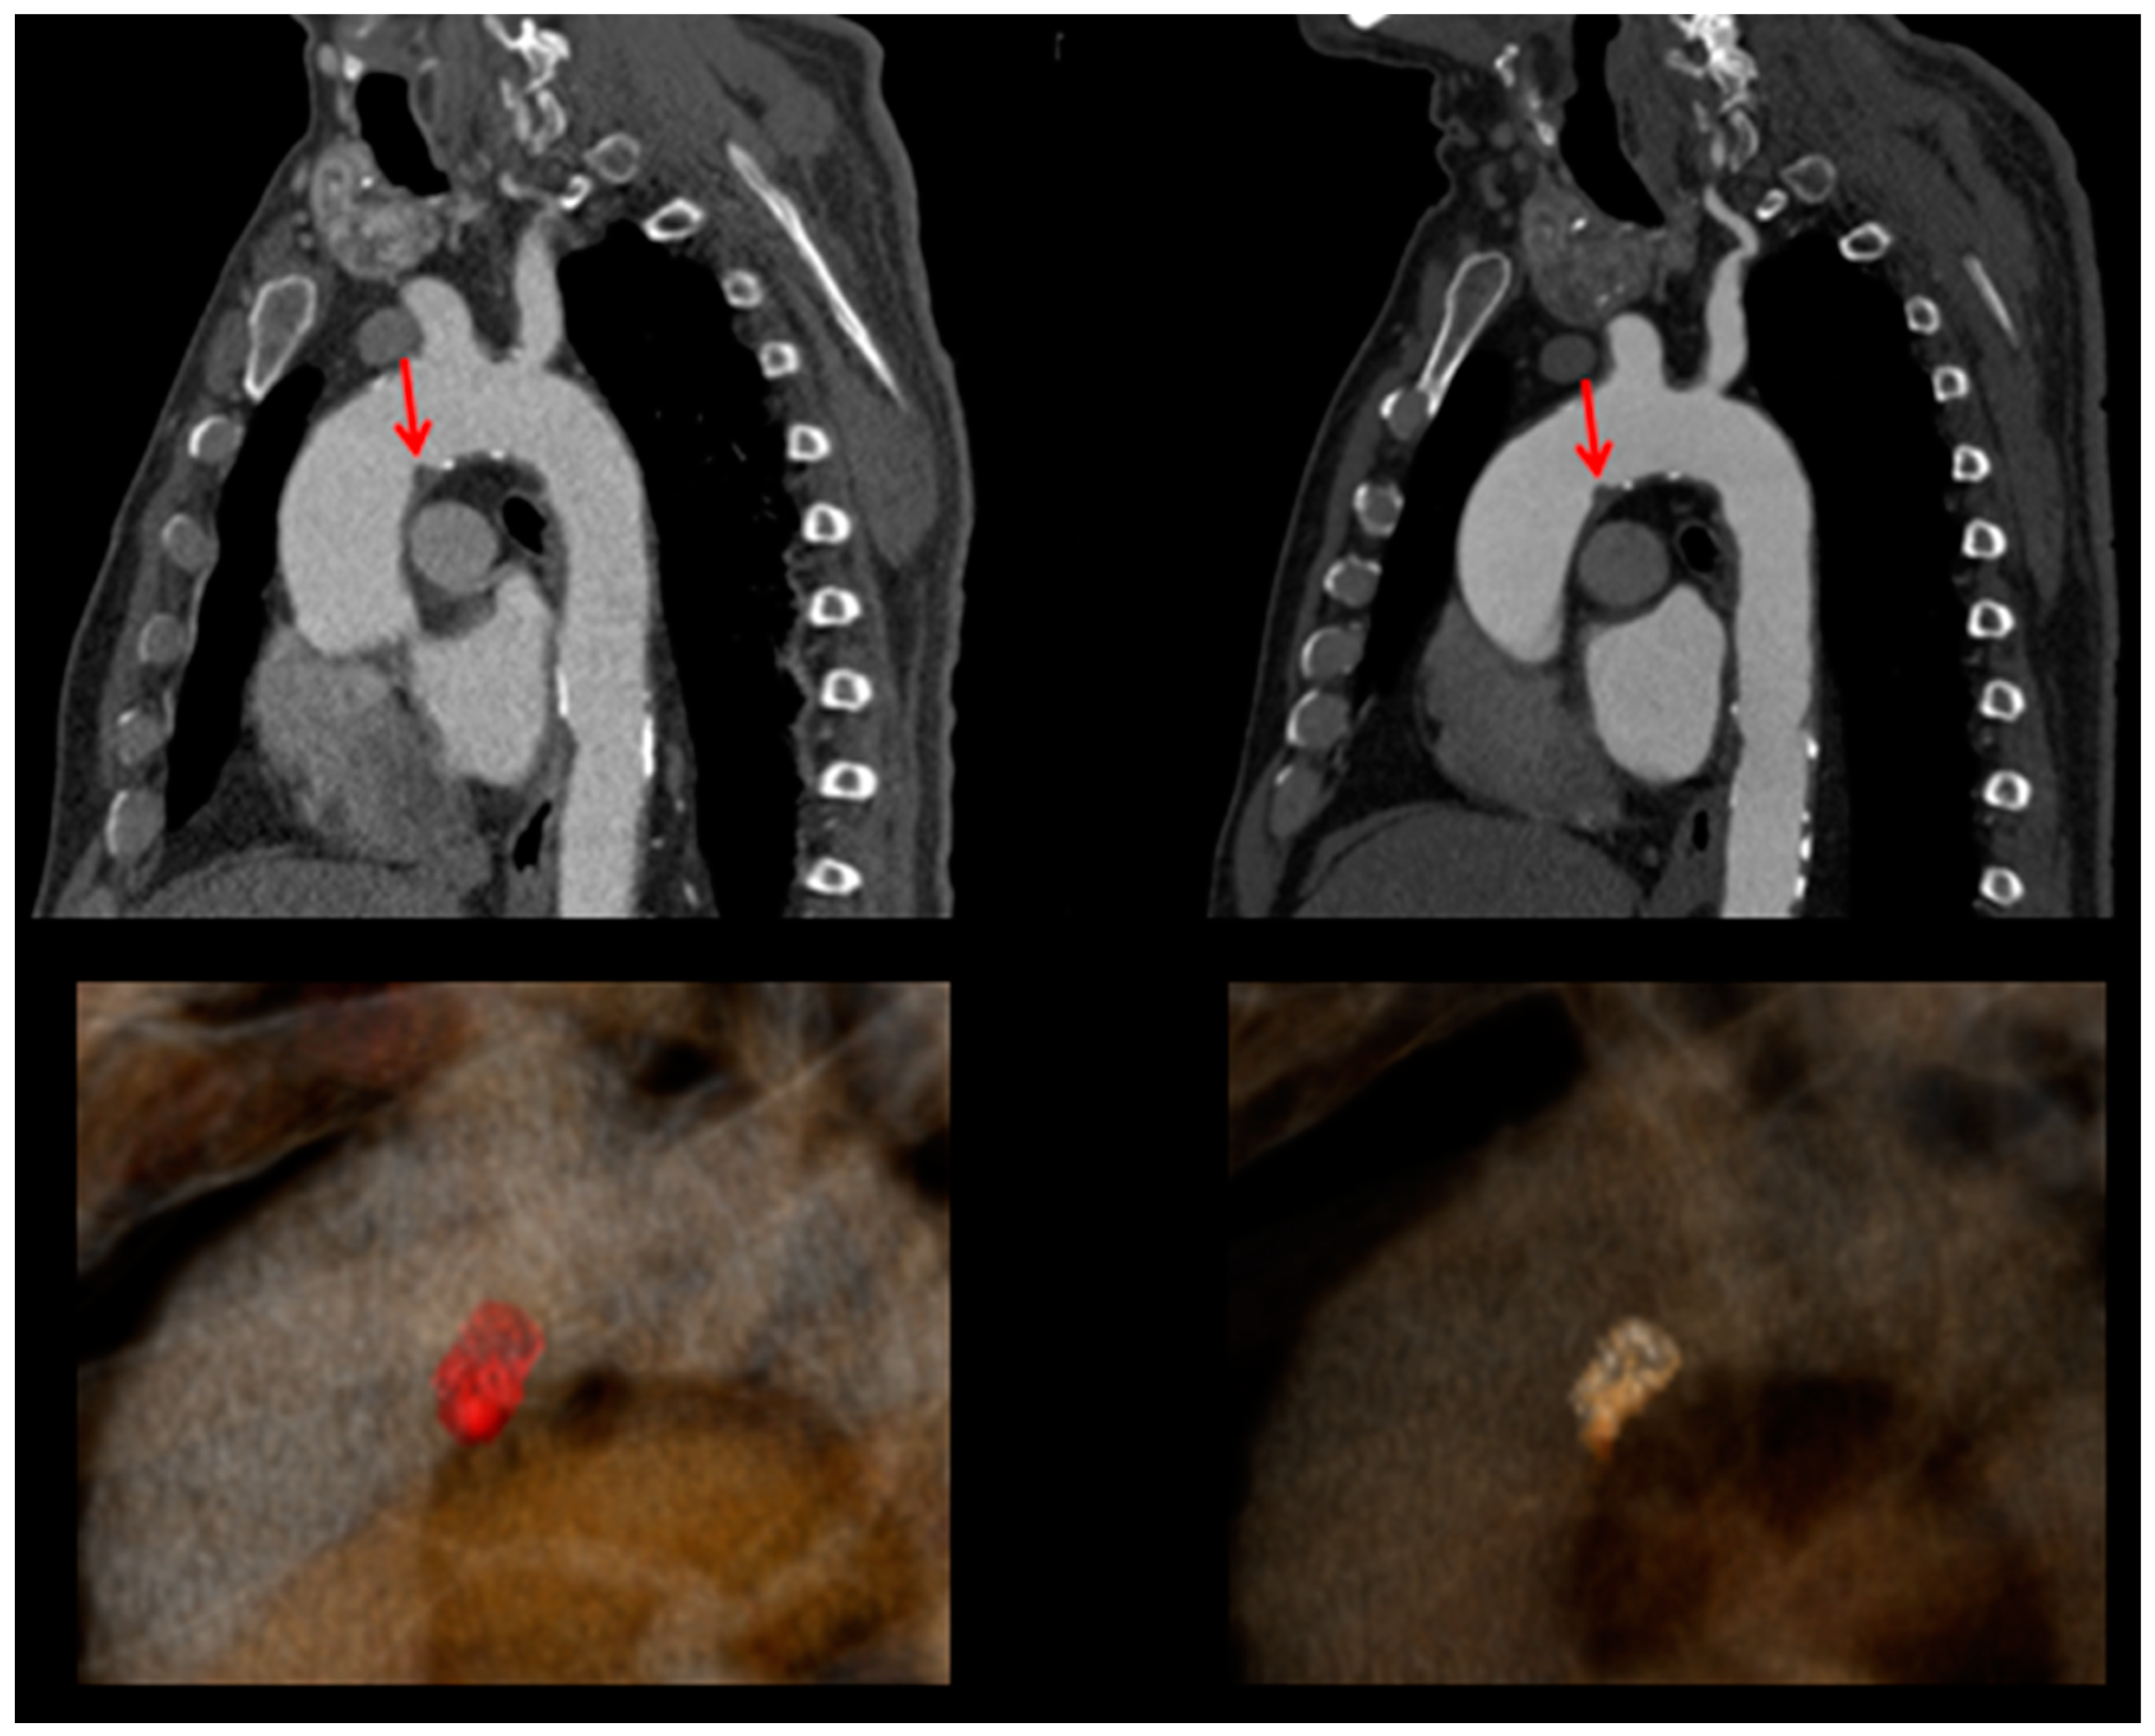

Unilateral Posterior Spinal Cord Ischemia Due to a Floating Aortic Thrombus: A Case Report

2. Case Presentation